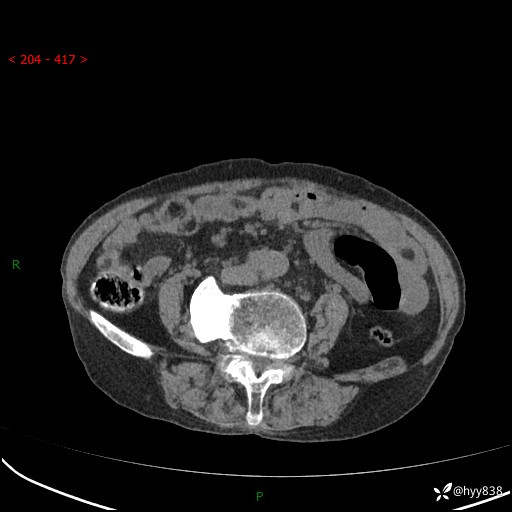

全腹部CT平扫